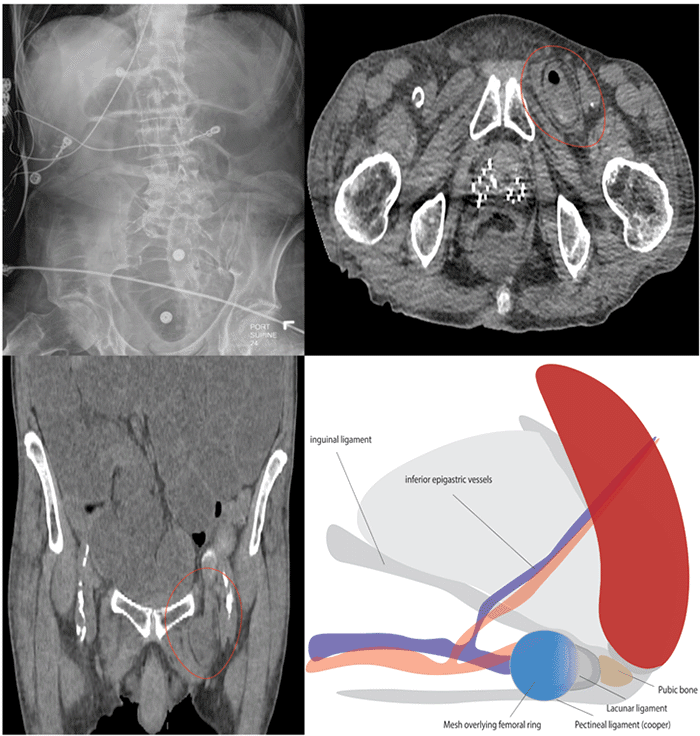

Physical examination revealed abdominal distention, and abdominal X-ray showed mildly dilated small bowel loops (Figure 1A). Ileus was suspected due to pneumonia (no hernias identified on exam). Management included nonoperative nasogastric tube decompression and bowel rest. Initial labs showed leukocytosis (WBC 33,000/μL) and pre-renal acute kidney injury (creatinine 3.2 mg/dL, BUN 100 mg/dL).

The patient’s condition worsened with atrial fibrillation, rapid ventricular response, and hypotension, prompting transfer to critical care. Five days after nasogastric tube removal (initial gas and stool passage reported), he developed renewed distention and witnessed aspiration. His respiratory status deteriorated, requiring high-flow nasal cannula (HFNC) and broader antibiotic coverage (vancomycin, cefepime, metronidazole). Non-contrast CT scan of the abdomen revealed mechanical small bowel obstruction due to a left-sided femoral hernia containing small bowel (Figure 1B, 1C). A concurrent chest CT scan confirmed aspiration pneumonia.

Figure 1. Imaging and Repair of Incarcerated Femoral Hernia. Published with Permission

A) Abdominal radiograph demonstrates dilated small bowel loops (suggestive of obstruction). B & C) Non-contrast CT scans reveal a femoral hernia containing a loop of incarcerated small bowel and ascites. The hernia sac is confined below the pubic tubercle, with compression of the femoral vein evident. D) Schematic illustration of minimally invasive mesh repair for incarcerated femoral hernia. The myopectineal orifice is closed with a mesh disc. The mesh patch (not shown) secures to the pectineal ligament, lacunar ligament, inguinal ligament, and the lateral aspect of the residual hernia sac. The disc overlies the femoral ring medially to the femoral vein, facilitating femoral canal closure.